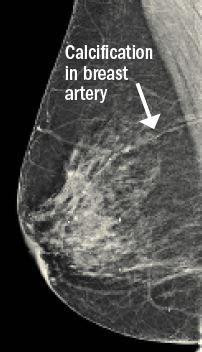

new analysisThe researchers developed a deep machine learning tool (a type of artificial intelligence) to predict heart disease risk over a 10-year period, based only on a woman’s age and features from her mammogram images (such as blood vessel calcium deposits and breast density). The analysis showed that the new tool was just as accurate as common heart disease risk calculators, which rely on age and medical data such as cholesterol and blood pressure values.